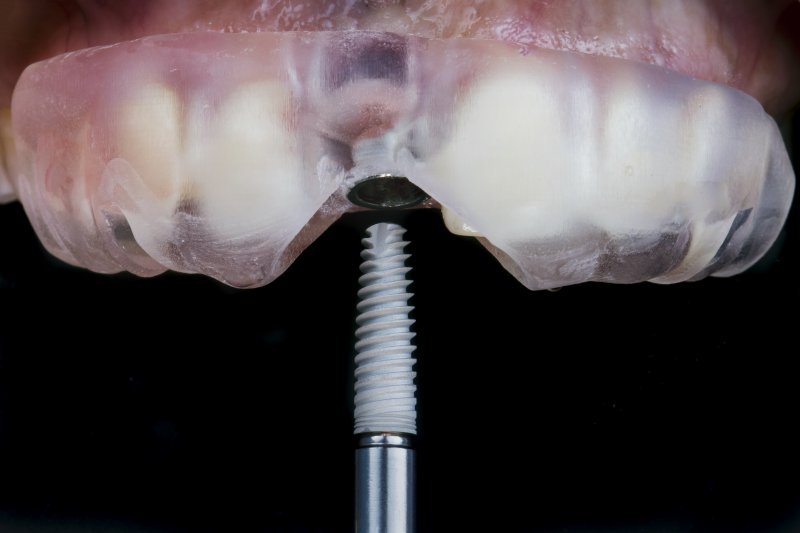

Pose d’implants dentaires

Prothèses sur implants

guides chirurgicaux à agdal, Rabat

Qu'est-ce qu'un guide chirurgical pour les implants dentaires - et pourquoi est-ce important ?

Lors de la pose d’implants dentaires, la précision est essentielle. C’est pourquoi nous utilisons un guide chirurgical sur mesure – conçu à partir d’un scan numérique de votre bouche – pour nous assurer que l’implant est placé à l’angle, à la profondeur et à la position parfaits.